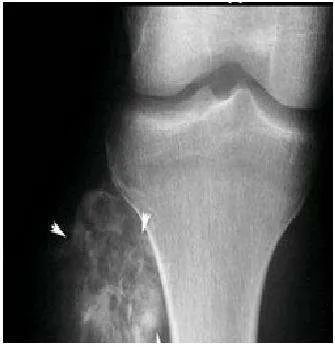

3、骨肿瘤的疼痛集中在固定点,比如说膝关节,容易出现红肿现象,但生长痛不会。总之,如果家里孩子喊腿疼的话,家长一定别大意,要观察孩子的具体症状,免得延误时机而不自知。实在不放心的话,最好去医院做下检查,由医生进行诊断。